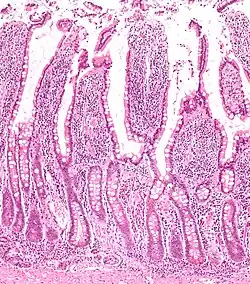

Criptas de Lieberkühn

Criptas de Lieberkühn ou criptas intestinais são glândulas tubulares simples encontradas entre as vilosidades da parede do intestino delgado e intestino grosso (colon). Secretam diversas enzimas, como sucrase e maltase, e possuem células especializadas na produção de hormônios e enzimas de defesa.[1]

Possuem epitélio simples colunar e fazem parte da camada mucosa do intestino.